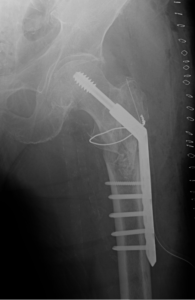

if the fracture is displaced, surgery may be needed to put the bone back into the correct position and fix the bone with Plates & screws or nails for adequate healing to occur.

- Hip Fractures.